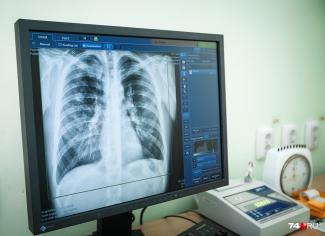

Иркутский филиал № 1 областной туберкулезной больницы по ул. Партизанской, 74 приглашает представителей прессы до 23 апреля в часы работы филиала проверить легкие - пройти флюорографическое обследование (при себе иметь паспорт или любой другой документ).

Результат флюорографии можно получить на следующий день. Обследование проводится БЕСПЛАТНО.